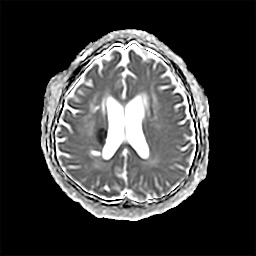

- CT / MRI 검사 : 뇌경색 또는 뇌출혈 영역을 영상을 통해 빠르게 진단 가능합니다.